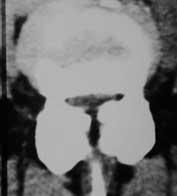

Similar to the cervical spine it is enough to initiate an X- ray or a nuclear resonance imaging. If the patient suffers from slipped vertebral bodies or a multiple stenosis it is most helpful to perform a myelographic imaging to get the best impression.